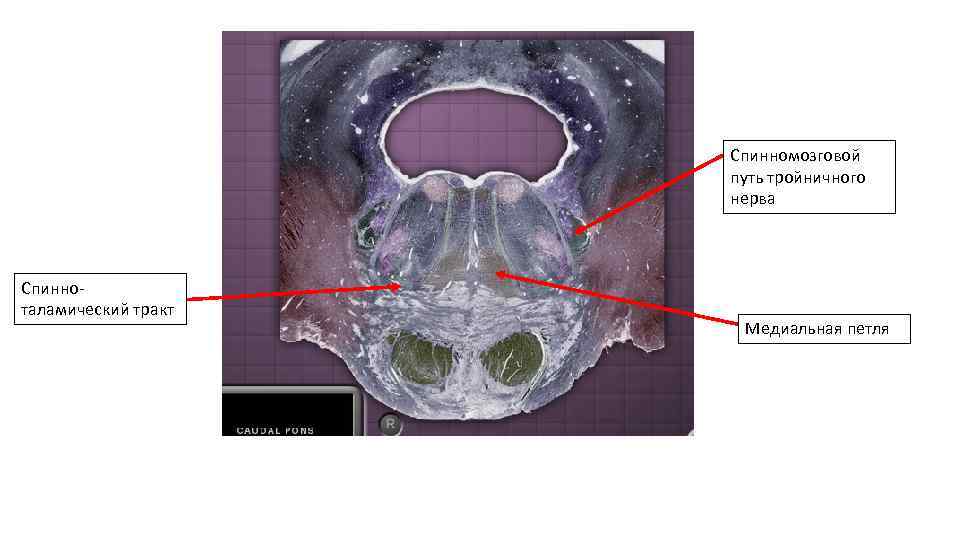

Спинномозговой путь тройничного нерва Медиальная петля Спинно-таламический тракт Спинномозговой путь тройничного нерва Медиальная петля Спинно-таламический тракт

Спинномозговой путь тройничного нерва Спинноталамический тракт Медиальная петля Спинномозговой путь тройничного нерва Спинноталамический тракт Медиальная петля